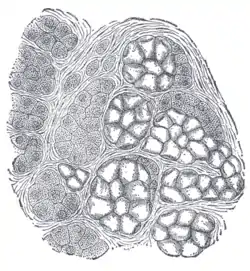

Alveoli of lacrimal gland.

Alveoli of lacrimal gland. Human submaxillary gland. At the right is a group of mucous alveoli, at the left a group of serous alveoli.